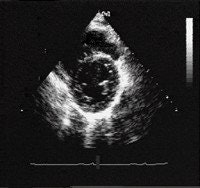

![]() |

| Patients with HCM have a characteristic thickening of the heart walls that can range from 14-60 mm. Particular thickening of one part of the heart, the interventricular septum, is characteristic of patients with HCM. The thick interventricular septum is marked with an asterisk. Images courtesy of the Hypertrophic Cardiomyopathy Program, St. Luke's-Roosevelt Hospital Center, New York City. |